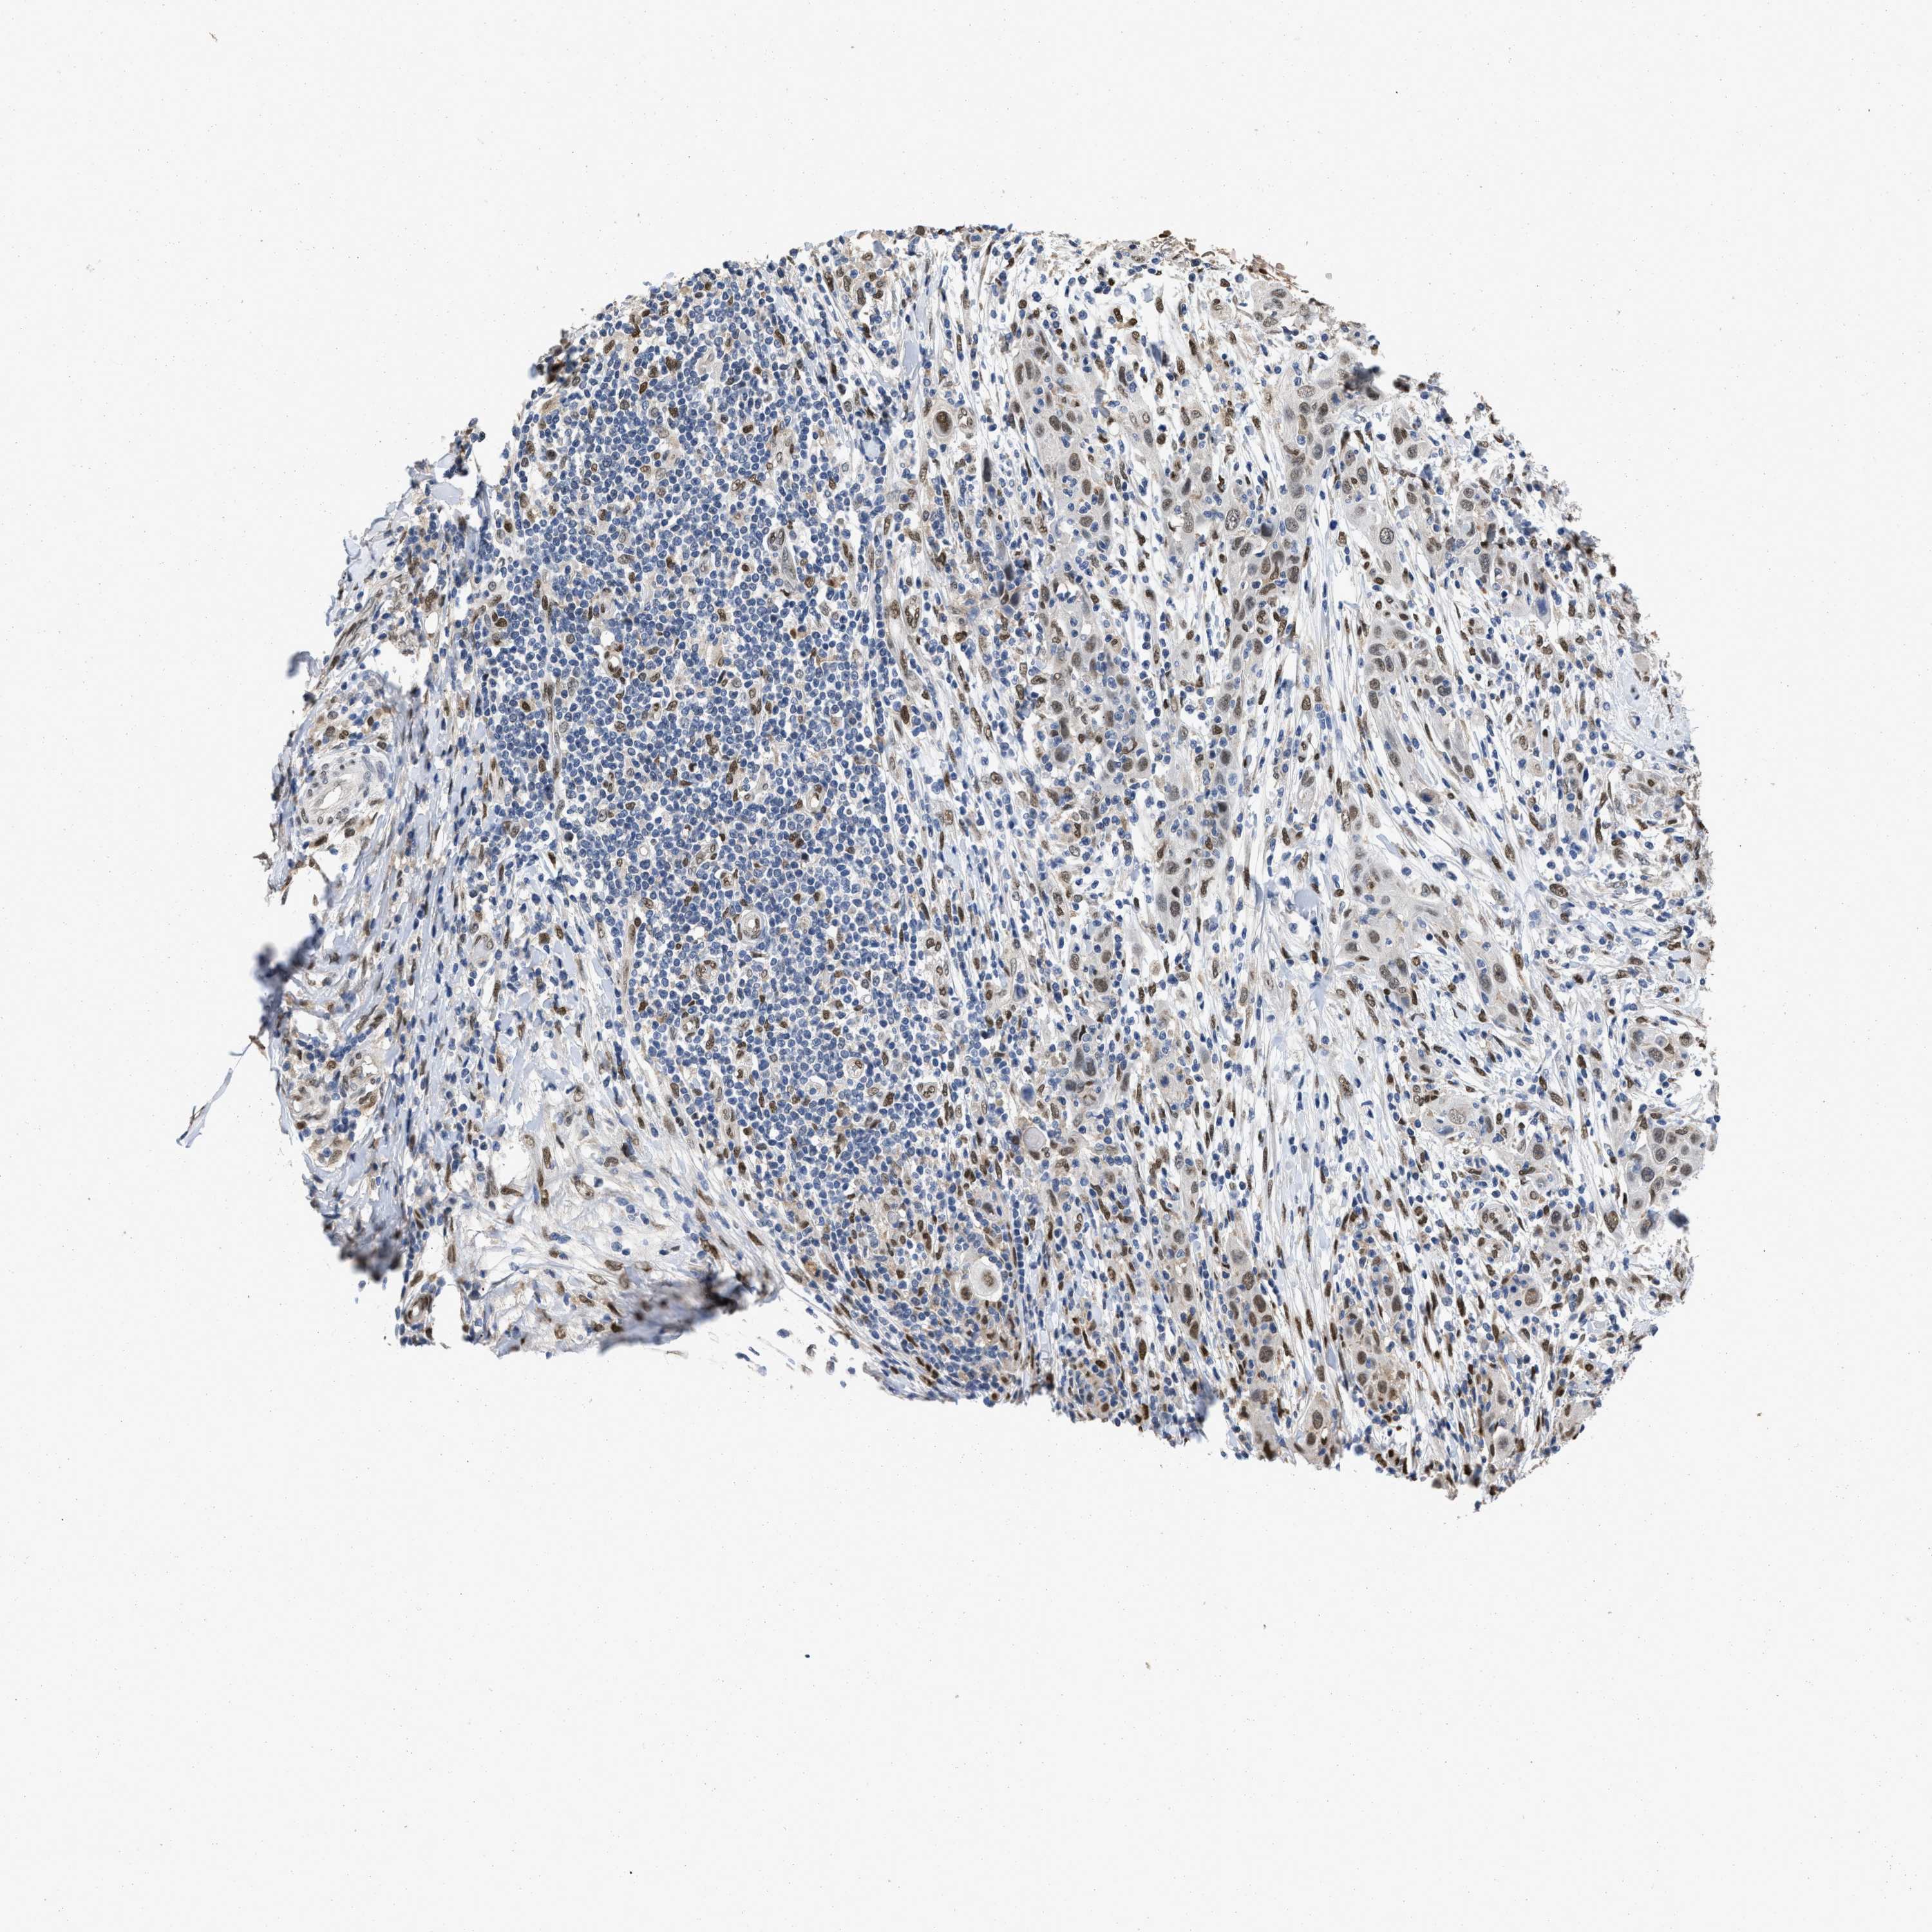

SKIN CANCER - Protein expressioni

A mouse-over function shows sample information and annotation data. Click on an image to view it in a full screen mode. Samples can be filtered based on level of antibody staining by selecting one or several of the following categories: high, medium, low and not detected. The assay and annotation is described here.

Antibody stainingi

Antibody staining in the annotated cell types in the current human tissue is reported as not detected, low, medium, or high, based on conventional immunohistochemistry profiling in selected tissues. This score is based on the combination of the staining intensity and fraction of stained cells.

Each image is clickable and will lead to virtual microscopy that enables deeper exploration of all samples and also displays staining intensity scores, fraction scores and subcellular localization as well as patient and tissue information for each sample.

Antibody HPA019123

Antibody CAB022602

Staining

High

Medium

Low

Not detected

Intensity

Strong

Moderate

Weak

Negative

Quantity

>75%

75%-25%

<25%

None

Location

Nuclear

Cytoplasmic/membranous

Cytoplasmic/membranous,nuclear

Squamous cell carcinoma in situ, NOS

Squamous cell carcinoma, NOS

Squamous cell carcinoma, metastatic, NOS

Basal cell carcinoma